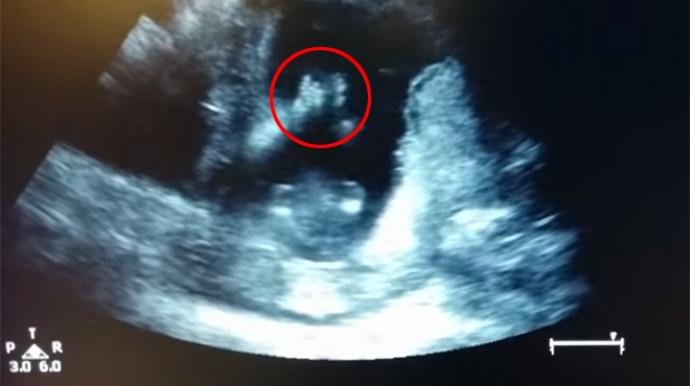

Ce futur bébé sera-t-il un vrai boute-en-train? Il semble en tout cas avoir des prédispositions à l'enthousiasme. Lors de l'échographie de la quatorzième semaine de grossesse, on peut l'apercevoir applaudir dans le ventre de sa mère.

Le voyant taper dans ses mains, la maman a décidé de l'encourager. "J'ai chanté une chanson avec le docteur et mon mari filmait", témoigne la mère, que l'on entend entonner "If you're happy and you know it clap your hands" ("Si tu as de la joie au coeur tape dans tes mains") sur Youtube. "Je n'oublierai jamais, le bébé a applaudi trois fois (...) C'était incroyable", commente-t-elle.

La vidéo, postée le 26 mars, a déjà été vue près de 4 millions de fois sur Youtube. Alors que certains internautes soupçonnaient un "fake", la mère a attesté à Today que les trois premiers "clap" étaient spontanés, sous-entendant que la suite était bien un montage. Le médecin "a rejoué la vidéo pendant que nous chantions afin qu'on aie l'impression que le bébé applaudissait", explique-t-elle.

"Les foetus font toute sorte de mouvements incongrus in utero sans même le savoir", confirme un obstétricien interrogé par le site. Mais "si le contact entre les mains est réel, il ne s'est produit qu'une fois et ils ont ensuite probablement réalisé un montage", selon ce spécialiste.